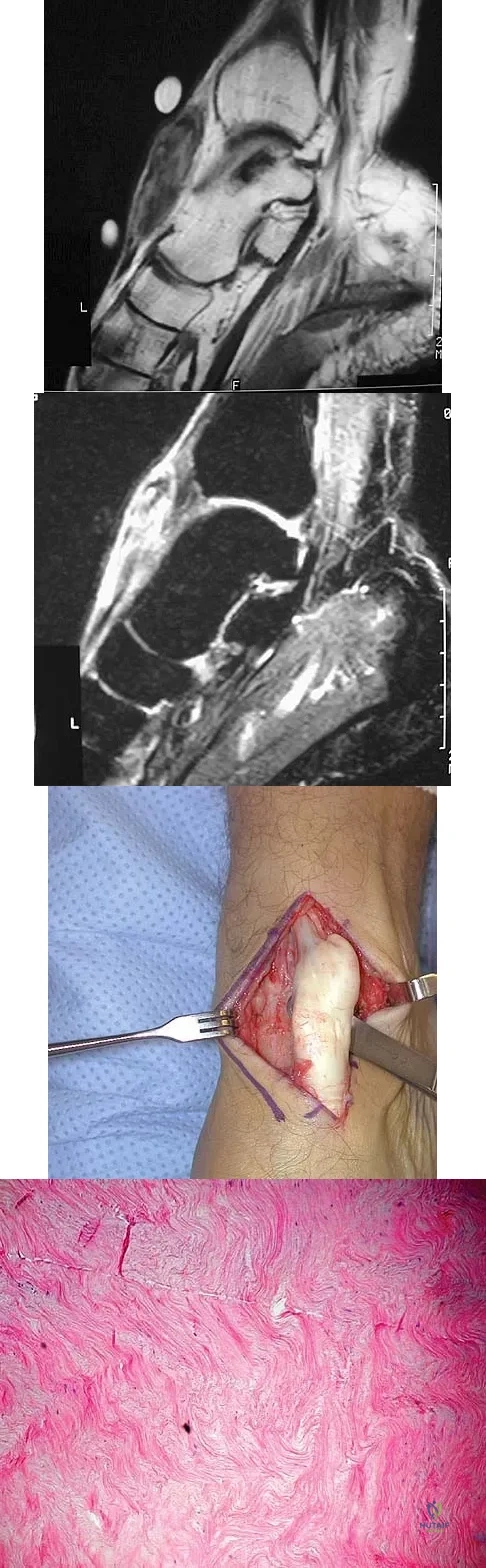

A 40-year-old man has a palpable mass over the dorsum of the ankle. He reports no history of direct trauma but notes that he sustained a laceration to the middle of his leg 6 weeks ago. Examination reveals a 4-cm x 1-cm mass. T1- and T2-weighted MRI scans are shown in Figures 12a and 12b. An intraoperative photograph and biopsy specimen are shown in Figures 12c and 12d. What is the most likely diagnosis?

Explanation

The findings are most consistent with a rupture of the anterior tibial tendon. The damaged area of tendon should be resected, followed by tendon reconstruction or tenodesis. The histology is not consistent with giant cell tumor of the tendon sheath, gout, or synovial sarcoma. Fibromatosis is characterized by a large number of spindle cells within the collagen background. Otte S, Klinger HM, Loreaz F, Haerer T: Operative treatment in case of closed rupture of the anterior tibial tendon. Arch Orthop Traum Surg 2002;122:188-190.